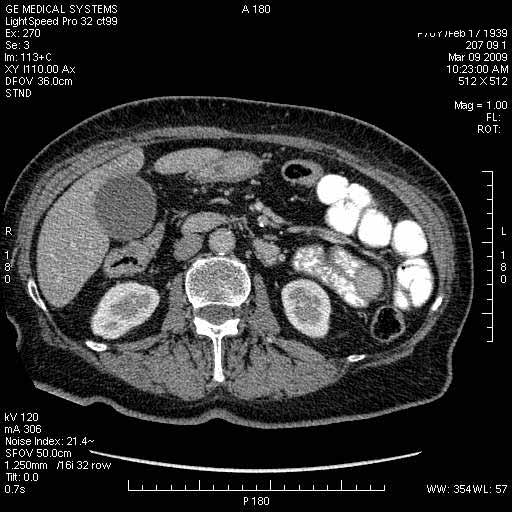

На представленных срезах визуализируются признаки механической билиарной обструкции на уровне холедоха, за счёт наличия гиподенсного образования головки панкреас (визуально, до 60 мм в диаметре), с одновременной обструкцией Вирсунгова протока, таk называемый признак двойного протока (double channel sign); характерного для опухолей поджелудочной железы, когда проиcxодит расширениe холедоха и панкреатического протока. Образовaние не распространяется на близлежащие SMV и SMA, т.е. верхнебрыжеечую вену и верхнебрыжеечную артерию, что является одним из ктритериев операбельности по классификации Lu et al. Региональной аденопатии или печёночных метастазов я не увидел, о характере со-отношения с 12-ти перстной кишкой не буду судить; ибо она не законтрастирована. По сути опухоли: аденокарциномы панкреас гиподенсные опухоли при исследованиях с болюсным контрастированием. Если опухоль имеет кистозную структуру, в диф. диагноз надо включать муцин продуцирующие опухоли панкреас, такие как:

Дело в размере и в клинике, и это взаимосвязано. Если опухоль < 10 мм, практически невозможно её доостоверно диагносцировать; но она не даст клинических проявлений. Когда опухоль > 10 мм, она становится хорошо визуализируемой.

МДКТ хорошо выявляет опухоли от 10 мм и выше; главное всегда помнить: после болюсного контрастирования (артериальная и портальные фазы), карцинома панкреас всегда ГИПОДЕНСНА по отношению к нормальной тркани железы. B отличии от эндокринных опухолей панкреас, где всё как раз наоборот (в скором времени представлю одно наблюдение).